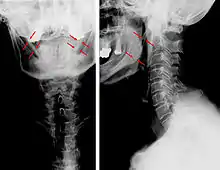

| Anteroposterior and lateral radiographs of cervical spine showing ossification of the stylohyoid ligament on both sides | |

Eagle syndrome (also termed stylohyoid syndrome,[1] styloid syndrome,[2] styloid-stylohyoid syndrome,[2] or styloid–carotid artery syndrome)[3] is an uncommon condition commonly characterized but not limited to sudden, sharp nerve-like pain in the jaw bone and joint, back of the throat, and base of the tongue, triggered by swallowing, moving the jaw, or turning the neck.[1] First described by American otorhinolaryngologist Watt Weems Eagle in 1937,[4] the condition is caused by an elongated or misshapen styloid process (the slender, pointed piece of bone just below the ear) and/or calcification of the stylohyoid ligament, either of which interferes with the functioning of neighboring regions in the body, such as the glossopharyngeal nerve.[4]

Eagle syndrome occurs due to elongation of the styloid process or calcification of the stylohyoid ligament, potentially compressing the nearby carotid arteryor glossopharyngeal nerve.[4] However, the cause of the elongation hasn’t been known clearly. It could occur spontaneously or could arise since birth. Usually normal stylohyoid process is 2.5–3 cm in length, if the length is longer than 3 cm, it is classified as an elongated stylohyoid process.[10] There are reports of eagles syndrome been elicited after wisdom tooth removal. [11]